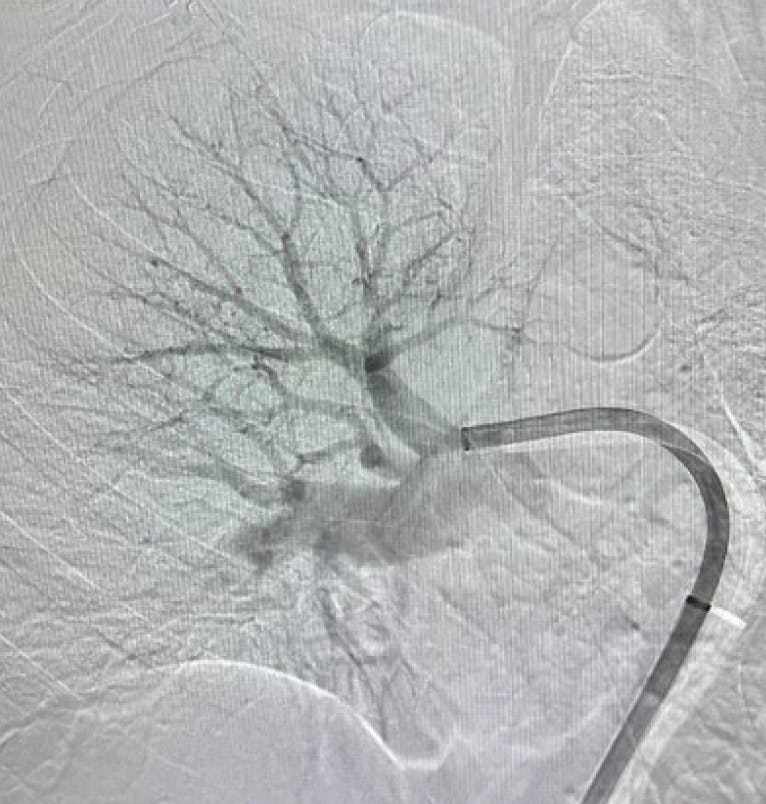

Figure 1. Right lobe initial angiogram.

Figure 1. Right initial angiogram.